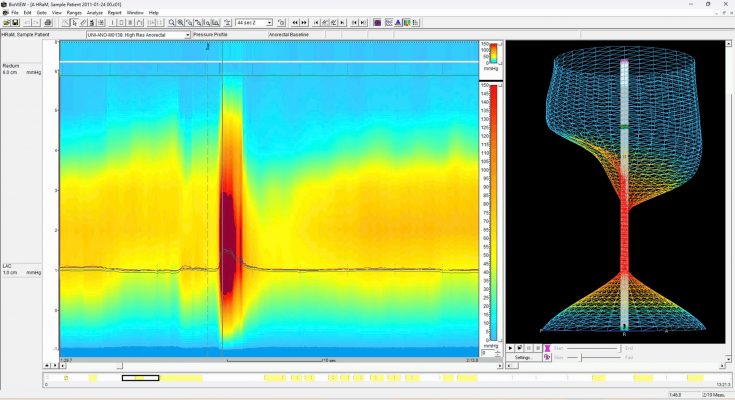

- Đo áp lực hậu môn trực tràng độ phân giải cao (HR-ARM): Sử dụng các cảm biến hiện đại để đo sự phối hợp giữa áp lực trực tràng và sự giãn nở của cơ thắt hậu môn. Đây là tiêu chuẩn vàng để xác định các loại hình đại tiện mất đồng vận (Type 1-4).